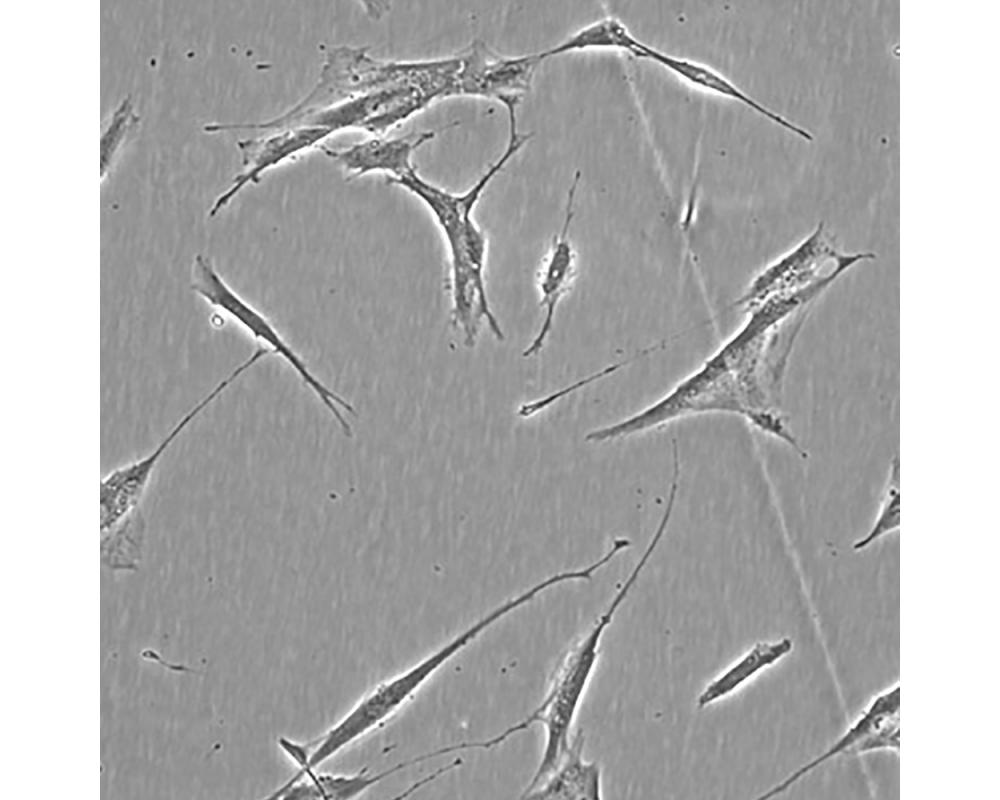

產品名稱 Hs 606.T

中文名稱 人乳腺癌細胞

組織來源 乳腺癌;女性

生長特性 貼壁

培養基 H-DMEM,90%;FBS,10%;雙抗。